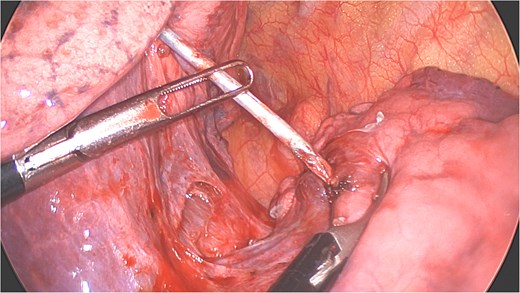

A clear minor pleural effusion and translucent scissural and para-aortic adhesions were visible. The adhesions of the pulmonary apex were released but no abnormality of the parietal pleura nor bone was visible. As the lung then collapsed, the pin became spontaneously visible protruding in the main fissure. As expected, the proximal part was in segment 2 and the distal half inside the apical segment of the lower lobe (S6) but it did not protrude outside of the parenchyma on either side (Fig. 4). The K-wire was easily removed by gently pushing back the parenchyma towards both extremities (Fig. 5). The pin seemed to be surrounded by a fine membrane that was coagulated at the visceral pleural entry point.

Distal part of K-wire stuck in segment 2 and the proximal part in the apical segment 6.